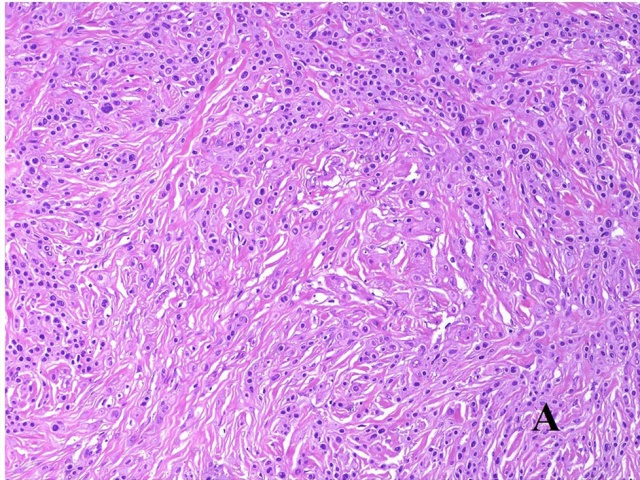

头颈部病理十大-促纤维增生性恶性黑色素瘤十大鉴别(二)

图片尺寸640x480